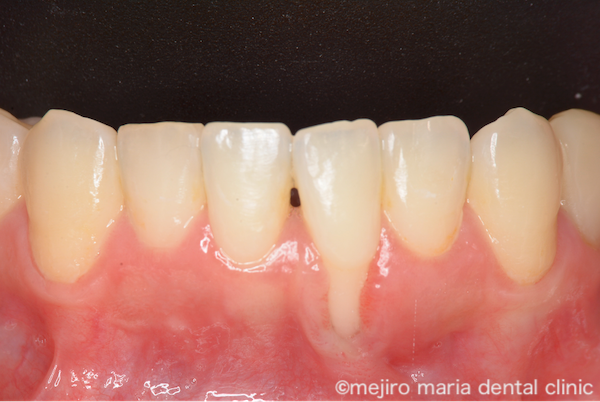

治療後の様子

術後経過3ヶ月後の状態です。術前に大きく歯茎下がりが確認できていた部位が改善しているのがわかります。患者様は術前にあった知覚過敏もなくなり、また審美的にも満足されています。今後は適切なブラッシングを継続していただくことで歯茎下りの再発を防いでいくことが必要です。